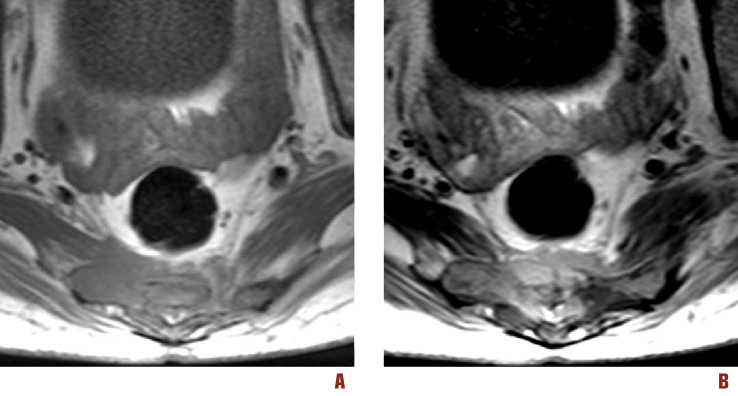

Figura 3. RM assiale T1 precontrasto (A) e RM assiale T1 postcontrasto (B) che mostrano l’invasione del mesoretto

Si rendeva pertanto necessario proseguire l’iter diagnostico presso ambiente specialistico internistico-ematologico. Le Figure 1-4 mostrano le immagini della regione sacrale e del mesoretto ottenute mediante RM e TC.